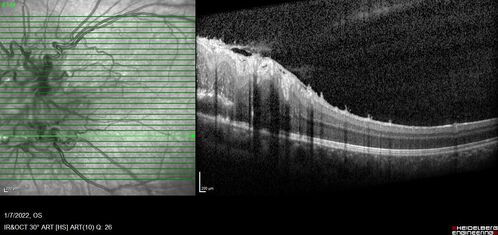

Combined hamartoma of the retina and retinal pigment epithelium

8 year old boy failed vision screening at school. VA 20/20 OD, 20/40 OS

Combined hamartoma of the retina and the retinal pigment epithelium